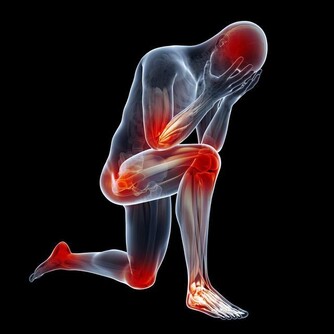

5、手足麻木

肝藏血,可以滋養人體的筋膜,使之活動自如。如果肝的氣血不足,則手足麻木、屈伸不利,甚至痙攣。另外,指甲和趾甲也是筋延伸到體表的部分,所以肝的氣血不足,還會表現為爪甲脆薄、顏色淺淡、變形脆裂等。